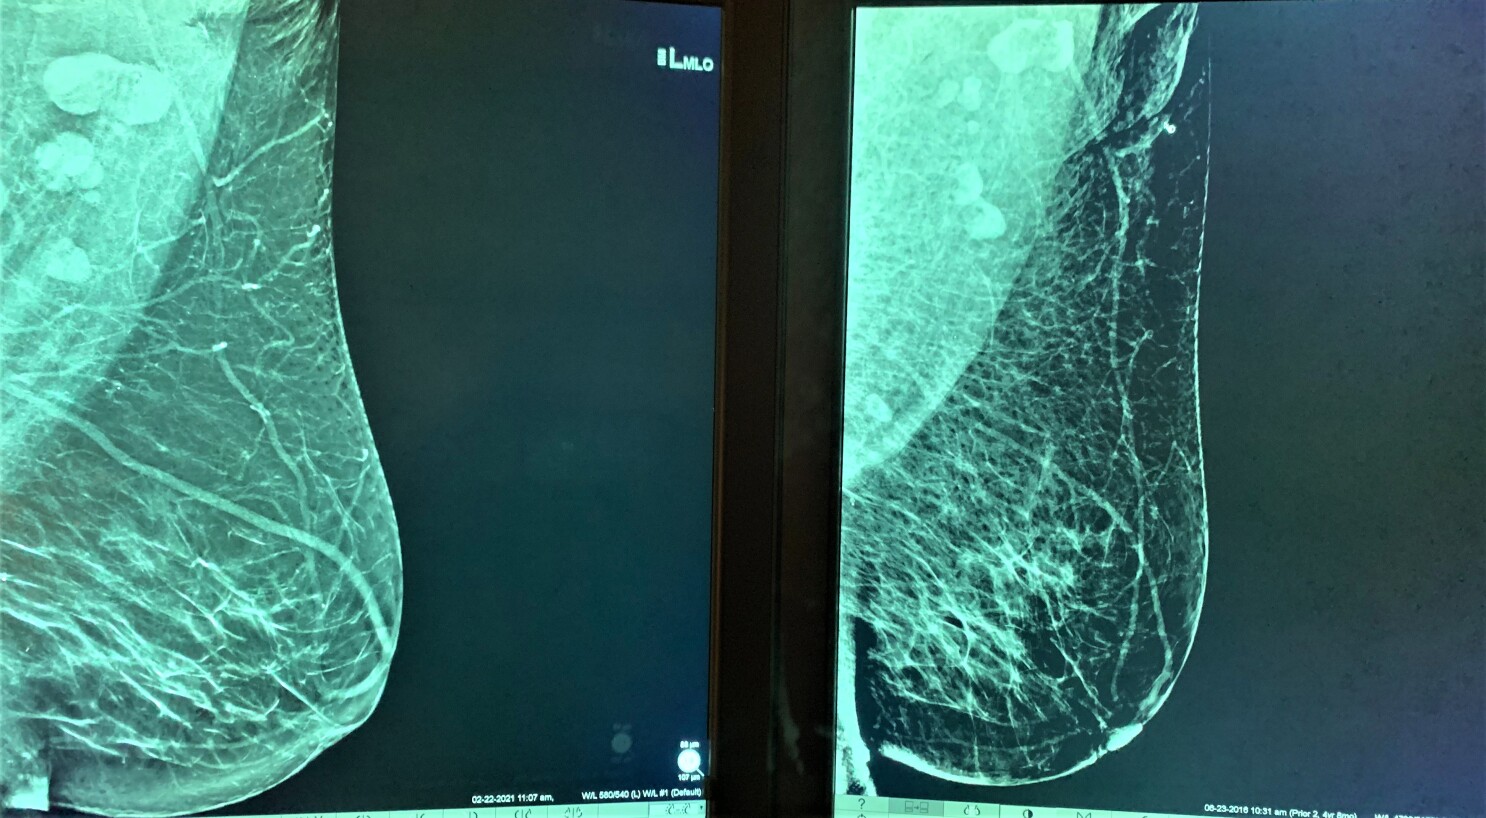

Swollen Lymph Nodes One Covid 19 Vaccine Side Effect Could Be Misread As Cancer Experts Warn Los Angeles Times